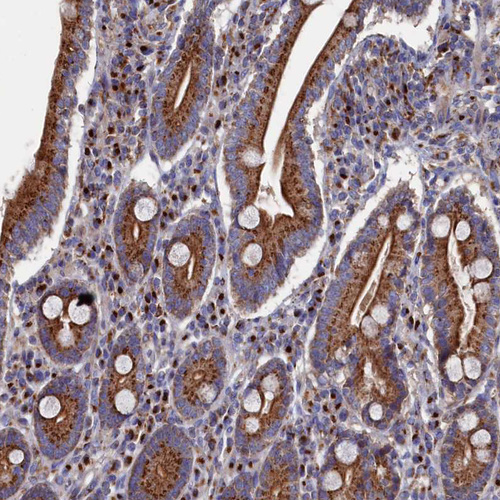

Immunohistochemical staining of human pancreas shows strong cytoplasmic granular positivity in exocrine glandular cells.